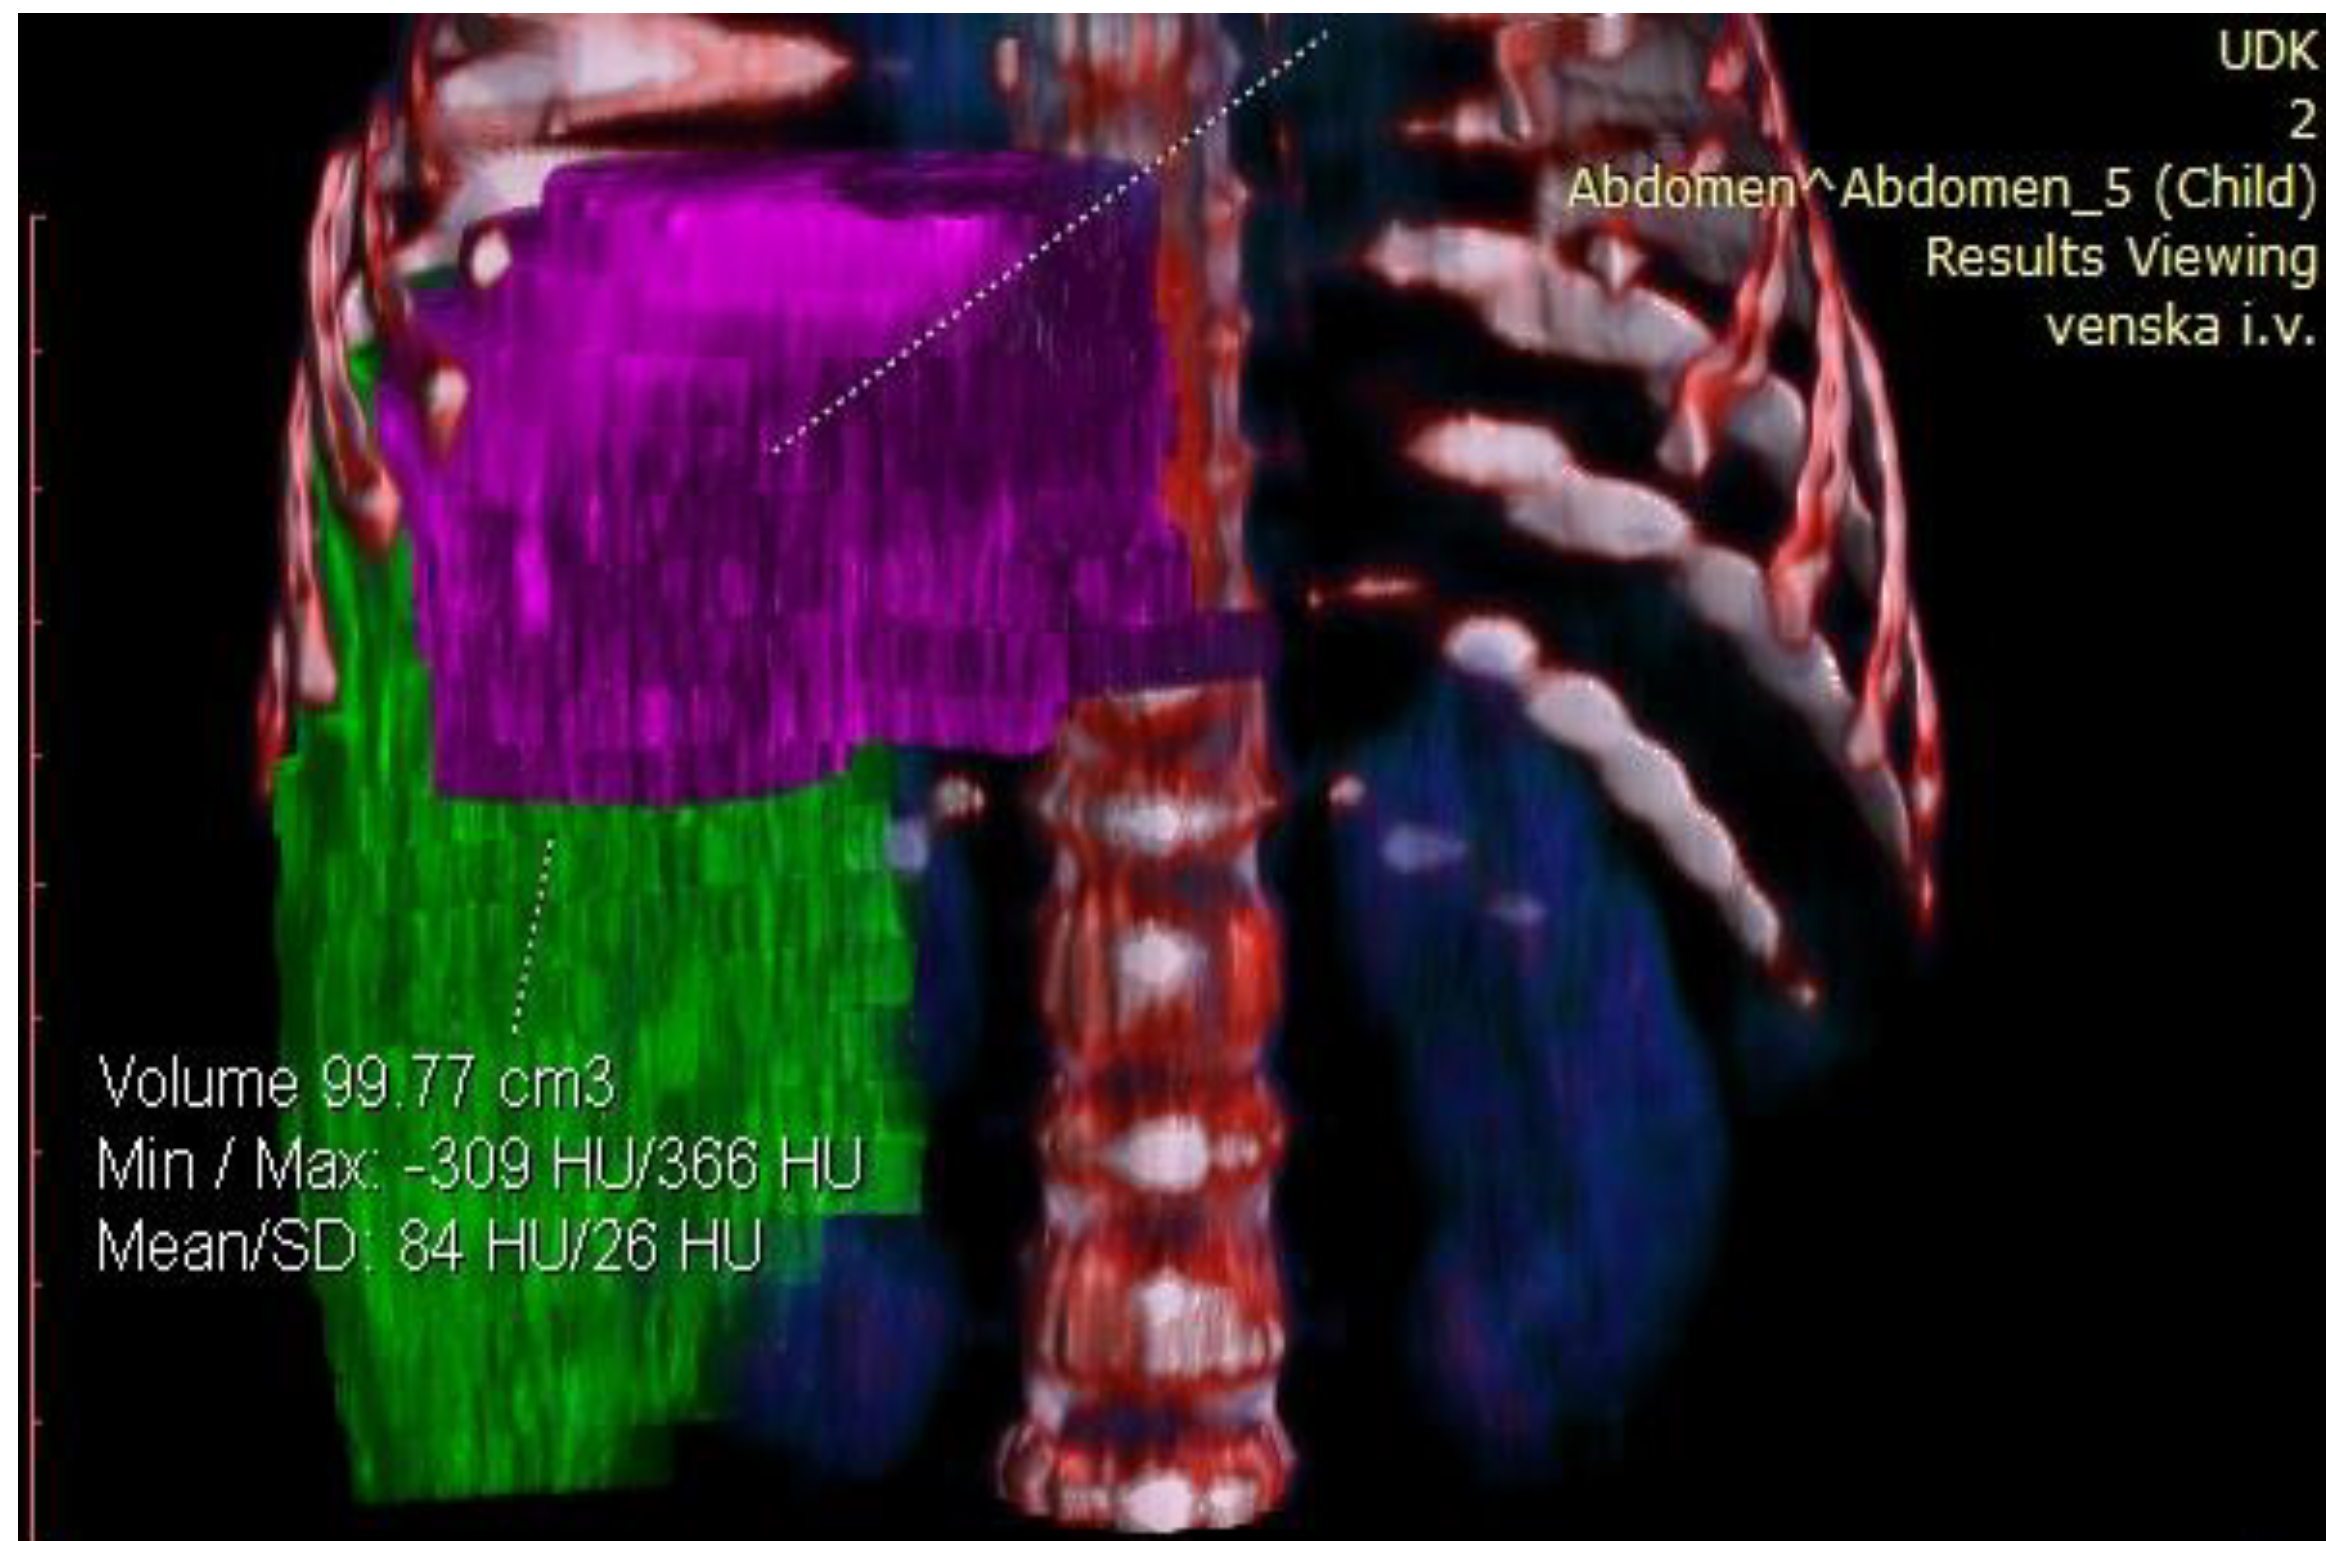

Considering the tumor’s size and localization, volumetric measurement was indicated to assess its resectability. Volumetric assessment of the liver showed that FLR was 99.77 cm3. The estimated total liver volume (ETLV) was 400.77 cm3, with an FLR/ETLV ratio of 24%, which was considered small for size after major hepatectomy and would lead to PLF (Figure 4 and Figure 5).

Preoperative volumetry of the liver showing total liver volume (TLV).

Preoperative volumetry of the liver showing future liver remnant (FLR).